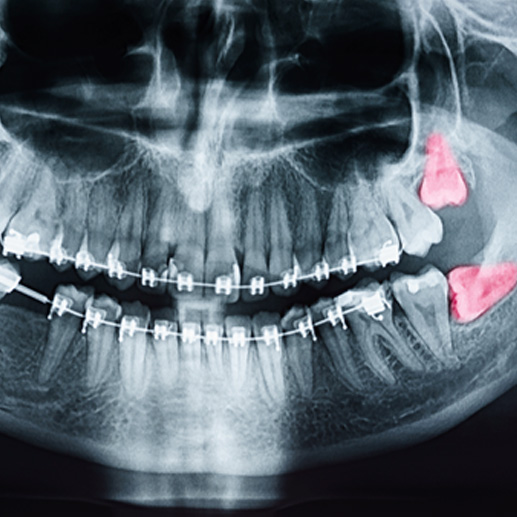

For many people, there simply isn’t enough room in the mouth for wisdom teeth to grow in properly. This is why at Sunset Avenue Dental, we monitor the development of our patients’ wisdom teeth to determine whether they can stay or need to be removed.

Most people are born with all four wisdom teeth, but some are born with fewer than that or none at all. Recent research suggests that somewhere between 5% and 37% of the population has fewer than four wisdom teeth, and this may be due to genetic factors. However, you may still have wisdom teeth if they do not erupt from the gum tissue, and the team at Sunset Avenue Dental will be able to detect hidden third molars with x-rays. While most people’s wisdom teeth will emerge when they are between the ages of seventeen and twenty-one, some will receive them sooner or later than that.